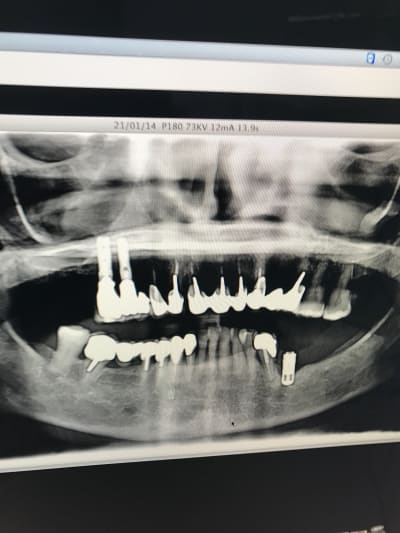

Je viens de récupérer un cas de prothèse sur implant d’un confrère. 14 15 jumelées avec 13 en extension. Le tout s’est dévissé. Je dois déposer et refaire….

et voila messieurs !

Ce sont des Serf... je bosse sur mac et c'est pas évident quand on ne maitrise pas mac pour sortir les radios. J'espère que ça conviendra

serf EVL donc connexion à plat...ce qui veut dire multiunits inutiles si tu n'utilises pas l'hexagone (ce qui est le cas déjà ici si tu étudies bien la rétroalvéolaire)

mais!: l'implant le plus mésial n'est pas dans un axe idéal ce qui veut dire que l'émergence de la vis sera merdique à gérer si tu veux faire de la transvissée...

tu n'as pas d'autre choix que de refaire de la scellée pour ce cas...et petit conseil, utilise des piliers indexés et non pas des piliers sans indexation comme ici...

amha çà c'est dévissé car les piliers n'ont pas étés mis dans la bonne position, ils ont été vissés/serrés de travers...la mastication les a fait revenir dans la bonne position...mais du coup ils ne sont plus serrés...

P.S: le vieil IMZ est bon pour le haricot...

PS: En 35-34 c'est l'exemple même de ce qui arrive dans un os D1. Certains appeleraient ça une peri implantite. .. à tort à mon avis. Il faut rétablir la vascularisation sinon re échec 🤔😕

C'est évident à la vue de ta pano. repenses au plan de traitement.